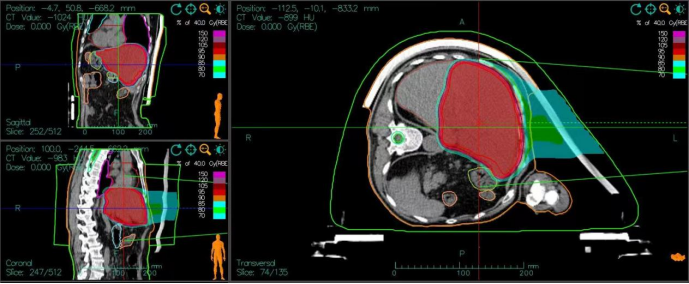

Second Course Plan:

Patient Position: Left lateral decubitus position.

Lesion Characteristics: Diffuse lesions within the liver parenchyma, with a Liver-PTV (Planning Target Volume) of approximately 606 mL.

OAR Constraints: Maintain an 8-mm margin away from the gastrointestinal tract to minimize radiation exposure.

Dose Prescription:

PTV40Gy(RBE): 40 Gy (relative biological effectiveness) delivered in 10 fractions (fx).

Boost Dose: 4 Gy(RBE)/fx.